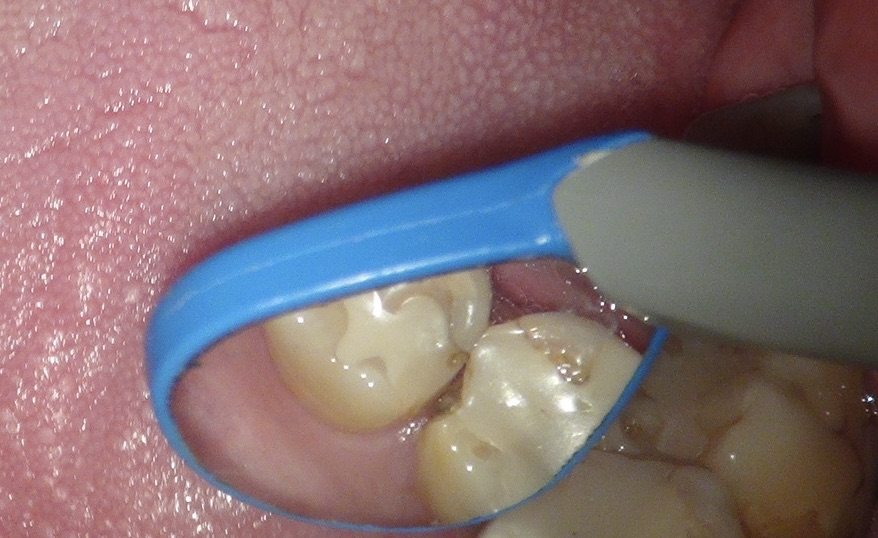

お口の中を見ると。

レントゲンの赤丸の部分がむし歯。